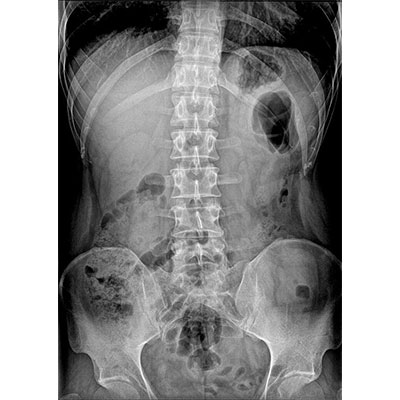

● 短曝光、高熱容,拍片數量多、效率高。

● 輕松應對大型體檢中心高強度的拍片要求。